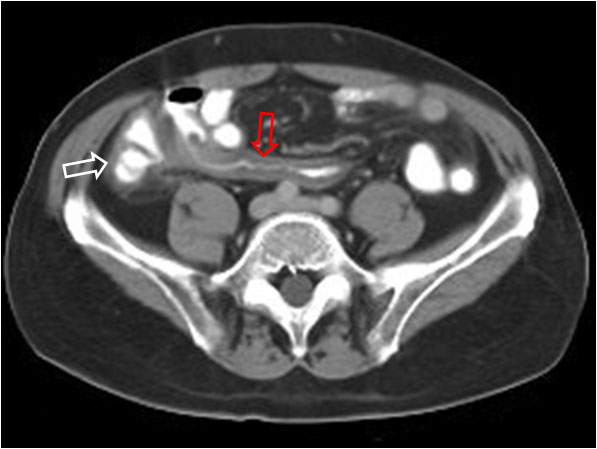

SIGNO DEL SANDWICH

Signo de linfoma abdominal tanto en la TC como en ecografía. Consiste en la presencia de masas adenopáticas que rodean y desplazan la arteria y la vena mesentéricas superiores sin comprimirlas.

La fotografía corresponde a un paciente con linfoma (flecha roja) que forma conglomerados adenopáticos que respetan los vasos mesentéricos (flecha blanca).